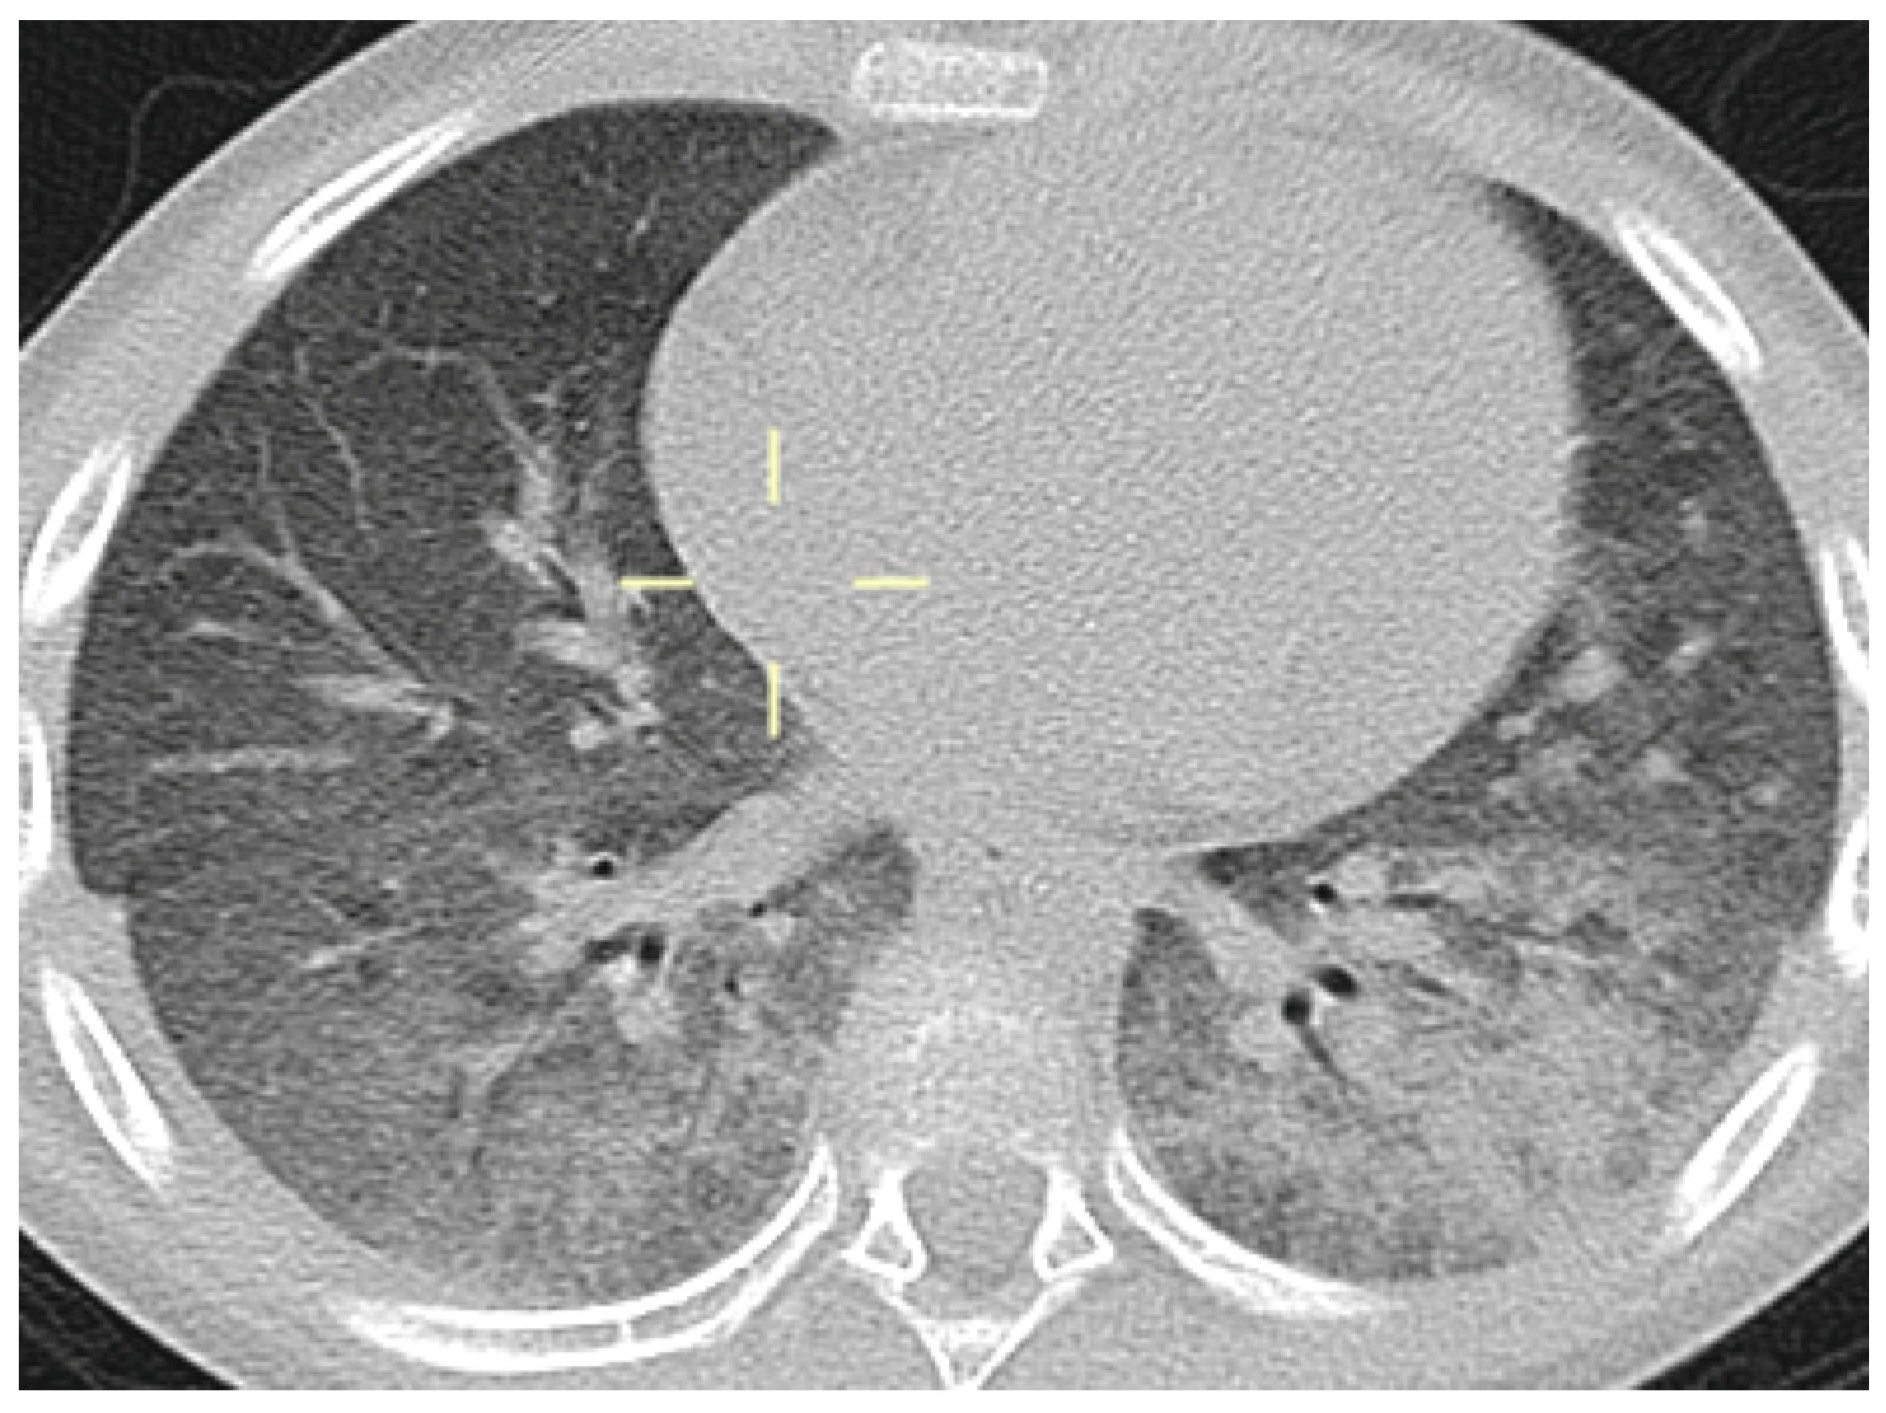

3.5. Radiological Features of PJP in the Study Population